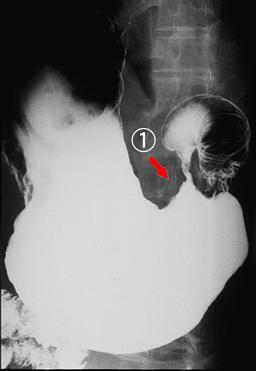

"Linfoma Maligno Precoz" central al antro, que mostró formación similar a Cáncer Avanzado de Estómago

[Image-ID:1638]

Tumor Maligno del Sistema Linfático/Linfoma Maligno

estómago(región)/mas de dos

Rayos X

diámetro mayor del tumor

40 -

sm